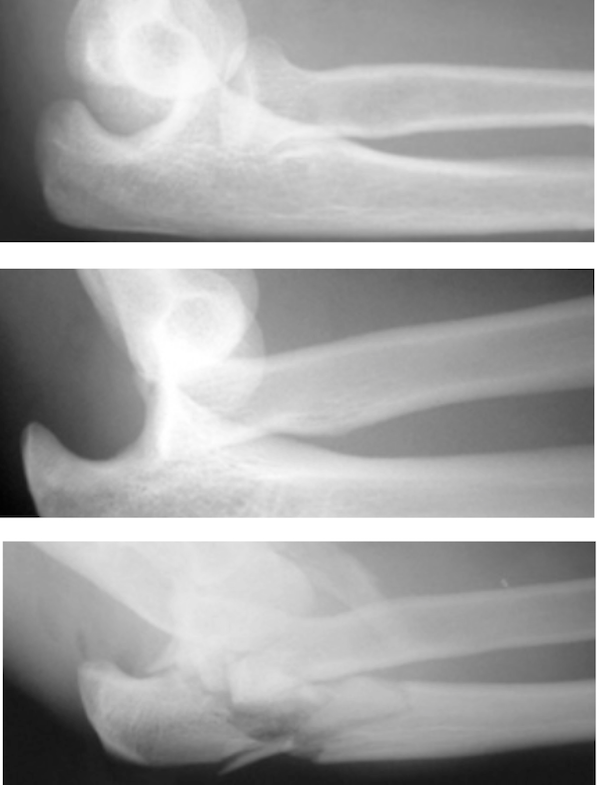

from pathologies.lexmedicus.com.au

Elbow dislocation How Serious Is A Dislocated Elbow This will help with the pain and will. A dislocated elbow occurs when the elbow bones no longer connect. The goal of immediate treatment of a dislocated elbow is to return the elbow to its normal alignment. It is a common injury in adults and children and often happens in tandem with bone fractures (breaks) and additional nerve and tissue. How Serious Is A Dislocated Elbow.